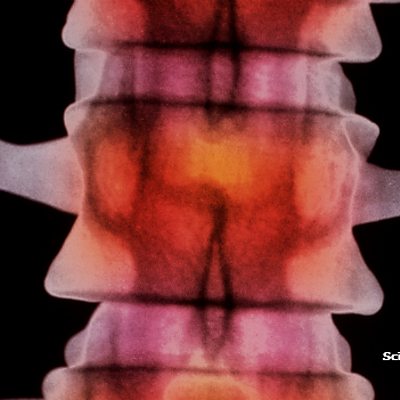

Scientists hope a device about the size of a matchstick will one day help people with spinal cord injuries get back on their feet. The stent-electrode recording array, or stentrode, could allow patients to control bionic limbs using only their thoughts. Thomas Oxley is a neurologist at the Royal Melbourne Hospital in Australia and one of the researchers behind this device.